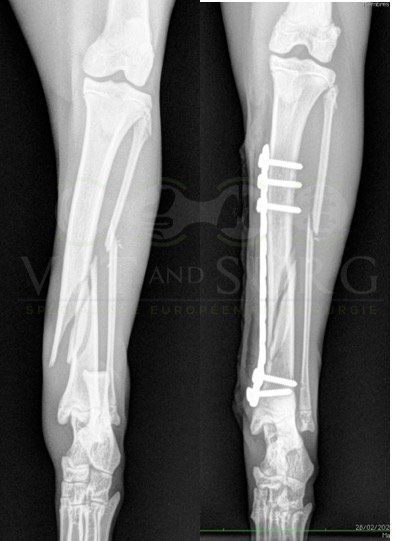

A la radiographie, une fracture de type Salter-harris 1 est diagnostiquée, avec déplacement de l'about discal.

Une réduction de la fracture par pose de 2 broches en croix a été réalisée.